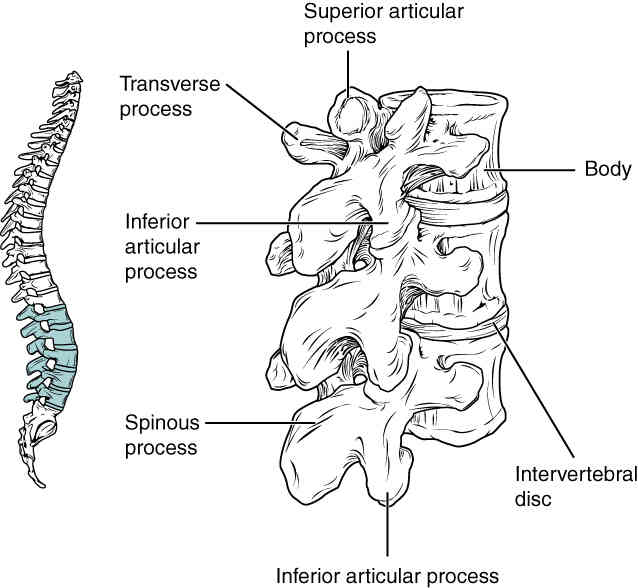

This page is under construction. For now, it is just a resource of the images found in the OpenStax Anatomy and Physiology Handbook. It wil slowly change into a revision tool. Each slide has a number. Use this to refer to the slide. When completed, it will have an unlabelled section, with labelled slides in parallel. On the unlabelled slides, write your answer and use the labelled slide to assess yourself. Keep track by also noting the number on each slide. Improvement at each attempt is important, more so than full marks on a first attempt.